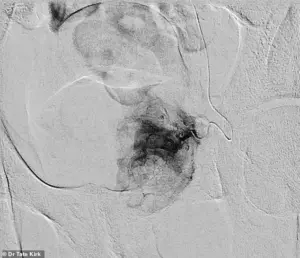

The procedure itself is a marvel of modern interventional radiology.

During pre-embolization, a catheter is carefully threaded into the artery supplying blood to the left half of the enlarged prostate.

Once in position, tiny particles are released to block blood flow to the targeted tissue.

Post-embolization, the affected area of the prostate experiences a dramatic reduction in blood supply, leading to shrinkage and relief of symptoms.

This targeted approach minimizes damage to surrounding tissues, a stark contrast to the more invasive techniques that have long dominated the field.